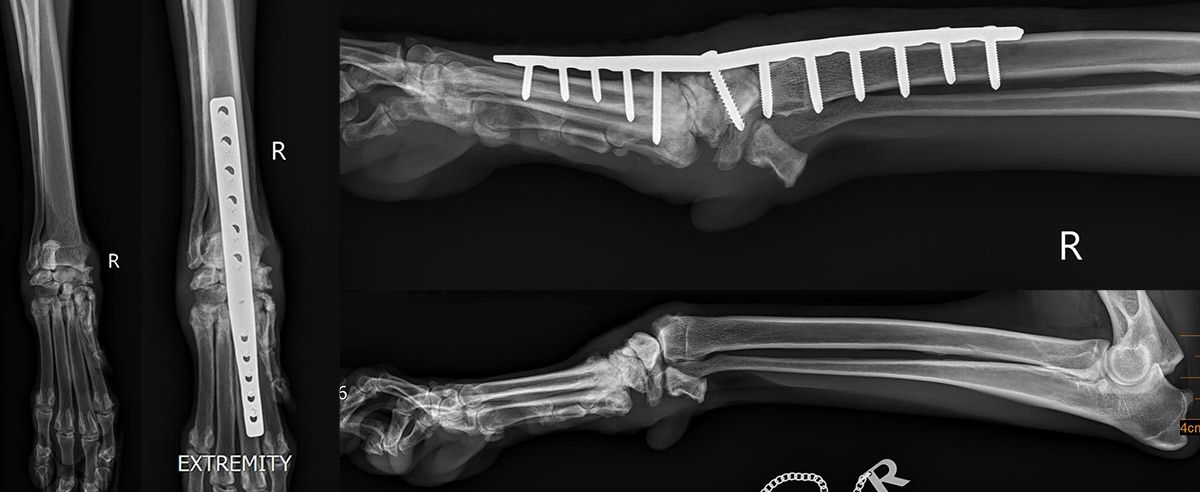

- Bildgebende Verfahren

• Röntgenaufnahmen

- Leeraufnahmen

- Stressaufnahmen